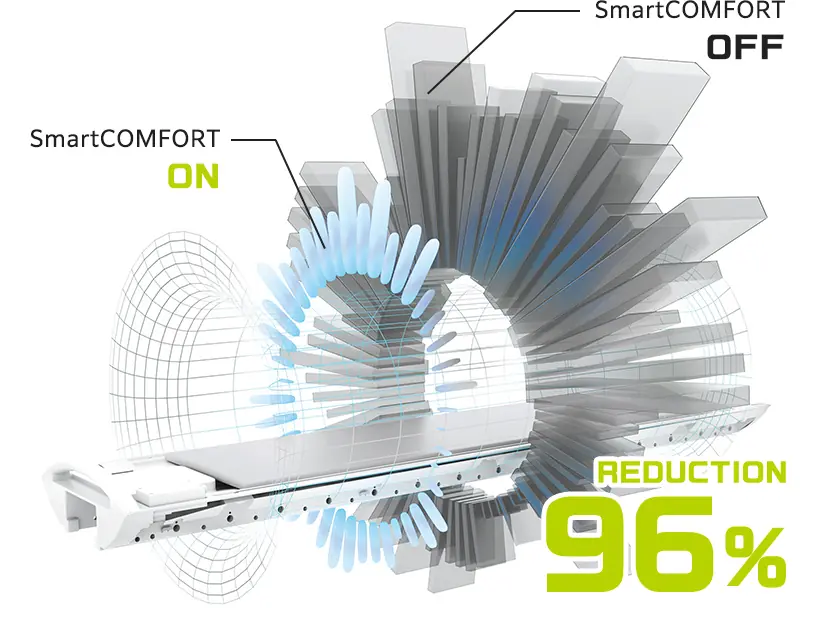

MRI akustik gürültüsünü azaltmak için çeşitli teknolojiler mevcuttur. Ancak, akustik gürültünün azaltılması genellikle görüntü kalitesini olumsuz etkiler ve tarama süresini uzatması nedeniyle rutin inceleme için uygun değildir. Diğer yaklaşımlar özel donanım gerektirir. SoftSound gürültü azaltma teknolojimiz, herhangi bir özel donanım olmadan görüntü kalitesini ve tarama süresini koruyarak akustik gürültüyü %96'ya*2 kadar azaltır.

*2 Görüntüleme koşullarına bağlı olarak